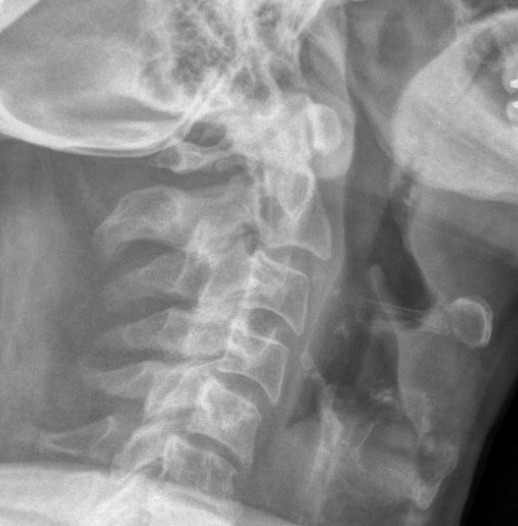

Xray

CT scan